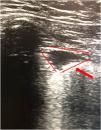

This is the case of a 61-year-old woman with obesity, hypertension, and chronic obstructive pulmonary disease (COPD) who presented to the emergency room with clinical signs of dyspnea and pleuritic pain in right hemothorax of 10-day evolution. She showed significant respiratory effort, which is why non-invasive mechanical ventilation (NIMV) was started. Thoracic X-ray looked normal, and the electrocardiogram performed revealed the presence of a dilated—though normocontractile—right ventricle. The thoracic ultrasound revealed the presence of a triangular hypoechogenic image of peripheral base that was consistent with right pulmonary infarction (Fig. 1). The axial thoracic computed tomography (CT) scan showed a repletion defect in the right pulmonary artery spreading towards the lobar branches plus pulmonary alveolar damage to the right upper lobe suggestive of associated pulmonary infarction (Fig. 2). The ultrasound provides extremely valuable additional information—essential at times—for the optimal management of the patients. The most indicative finding on the thoracic ultrasound of pulmonary thromboembolism (PTE) is the presence of triangular hypoechoic lesions and pleural base surrounded by a pleural line of normal aspect with or without associated pleural effusion.